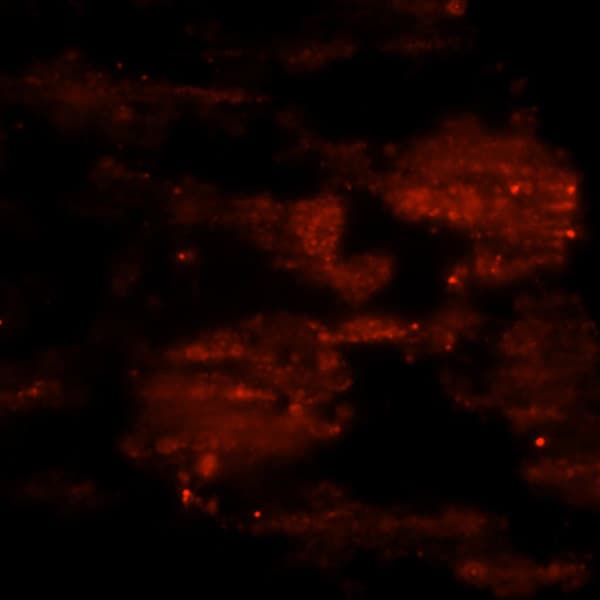

Phalloidin staining in liver tissue

Phalloidin staining in liver tissue.